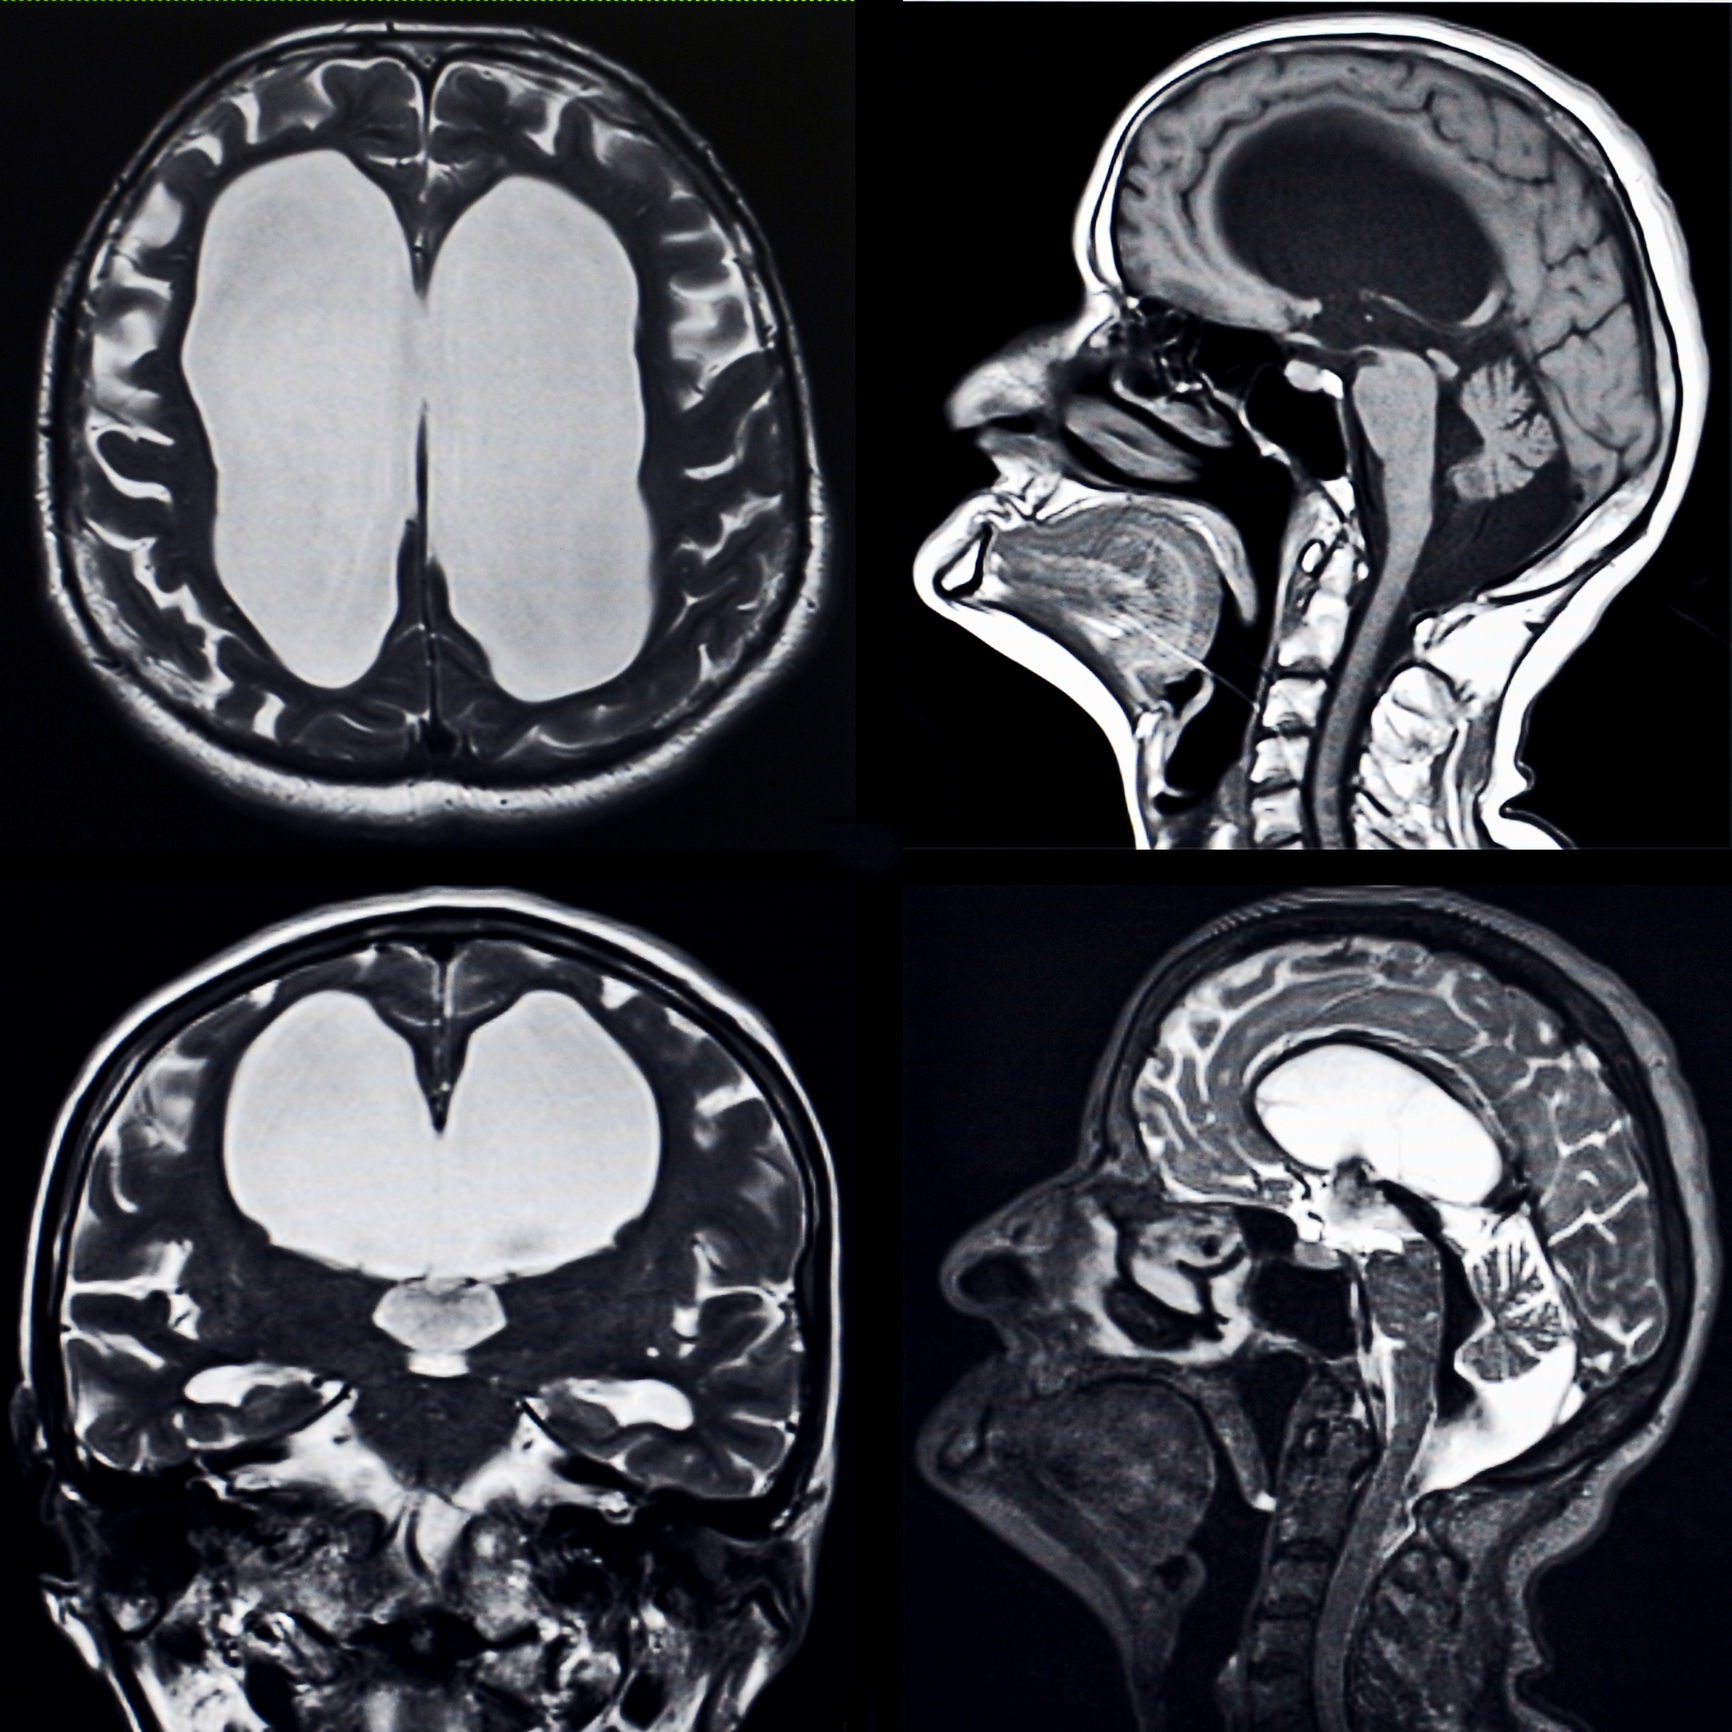

【腦積水】美國女子抑鬱症6年服藥不果 持續記憶力衰退、脾氣暴躁檢查驚現嚴重腦部積水

自2020年9月,克洛伊的家人發現她的情況越來越糟,因此花了約18萬美元(約141萬港幣),將她送往當地的心理治療機構長達6個月。直到醫生覺得不對勁、將克洛伊送急診做腦部檢查,才發現她有「腦積水」,且屬非常嚴重,不過藉手術清除,克洛伊恢復極快,在3個月後,她不但情緒問題消失,也重新回歸日常生活。